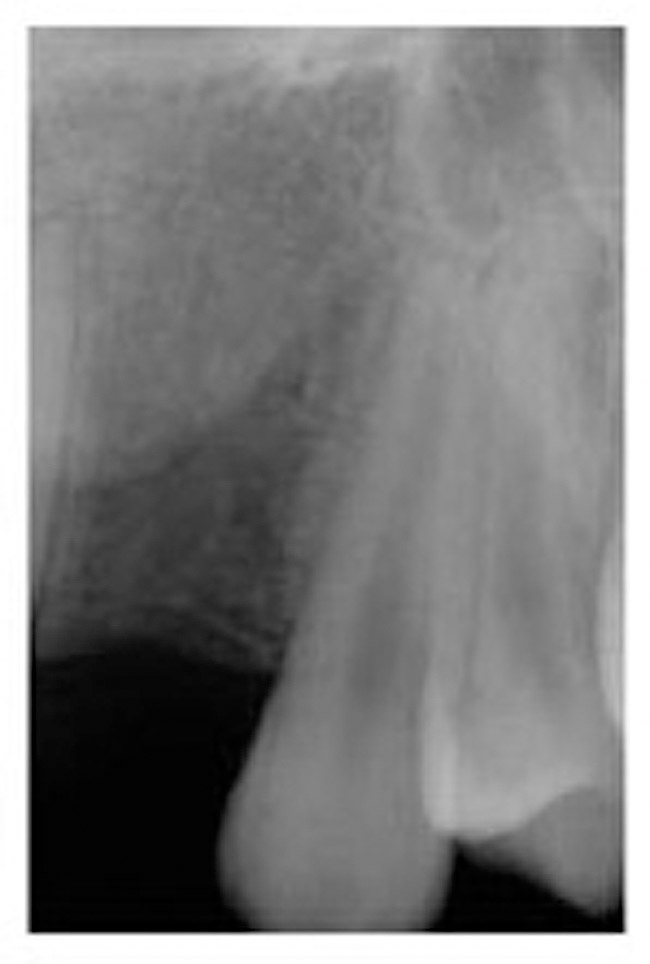

Figure 2  Pretreatment digital radiograph, right lateral incisor.

Figure 2

A 19-year-old non-smoking female presented for tooth replacement at the maxillary right and left lateral incisors, which were congenitally missing (Figure 1). The post-orthodontic result was adequate for the placement of 3-mm one-piece small-diameter implants. The preoperative radiographs can be seen in Figure 2 and Figure 3. The pretreatment clinical view in Figure 4 and Figure 5 shows the small intertooth space present in the lateral incisor areas. One of the most challenging tasks with congenitally missing lateral incisor cases is to create an acceptable soft tissue emergence profile from a crestal profile that is flat from the mesial of the canines to the distal of the centrals (Figure 4 and Figure 5). After pretreatment planning which consisted of a complete medical and dental history, radiographic analysis, and upper and lower study models mounted by a facebow transfer technique, the fabrication of a TempStent II surgical guide was completed. Figure 6 and Figure 7 show the occlusal view of the TempStent II guide on the study cast and in the oral cavity, respectively.